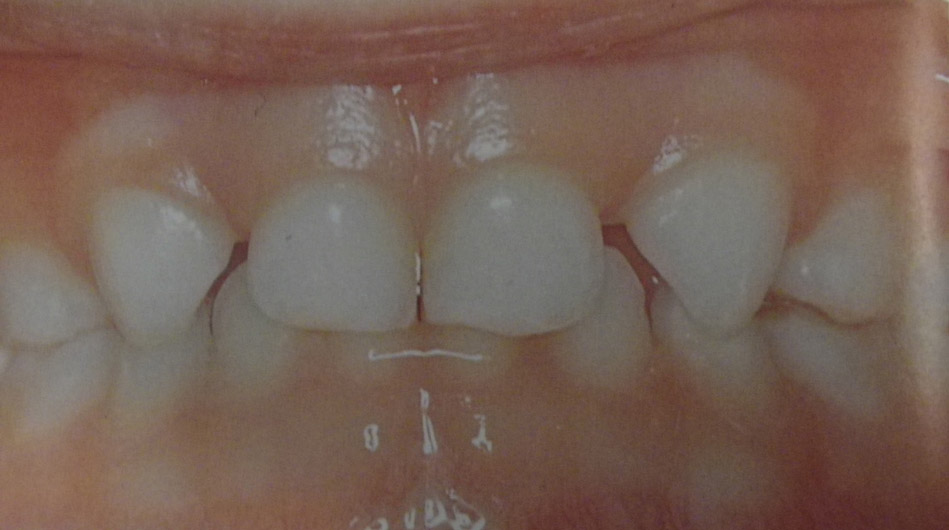

Τερηδόνα βρεφικής και νηπιακής ηλικίας ή τερηδόνα θηλασμού

Η τερηδόνα βρεφικής και νηπιακής ηλικίας εμφανίζεται σε μικρά παιδιά ηλικίας 2 έως 5 ετών, τα οποία έχουν τερηδονισμένα ένα ή και περισσότερα νεογιλά δόντια. Η τερηδόνα αυτής της μορφής οφείλεται σε λάθος τρόπο διατροφής του παιδιού και μπορεί να εξελιχθεί γρήγορα και σε μεγάλη έκταση επηρεάζοντας το σύνολο το δοντιών που βρίσκονται στο στόμα.

Η κυριότερη αιτία εμφάνισης της τερηδόνας αυτής της μορφής είναι το τάισμα με το μπιμπερό ενώ το παιδί κοιμάται. Κατά τη διάρκεια του ύπνου η ποσότητα του σάλιου μειώνεται και το γάλα, ανεξάρτητα αν περιέχει ή όχι ζάχαρη, παραμένει πάνω στα δόντια και προκαλεί τερηδόνα. Ακόμη και το μητρικό γάλα μπορεί να έχει τις ίδιες συνέπειες, εφόσον το παιδί θηλάζει κατά βούληση κατά τη διάρκεια της νύχτας.